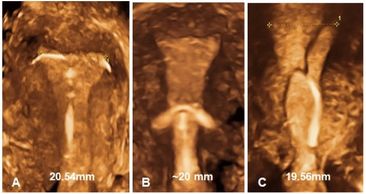

Normal position of an IUD seen on coronal 3D images.

Low and mildly oblique position of an IUD seen on coronal 3D images.

A, normal; b, low position; and c, oblique position of IUDs, seen on coronal 3D images.